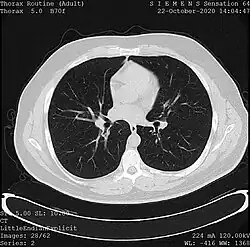

One frame of a CT scan of the chest showing the heart and lungs